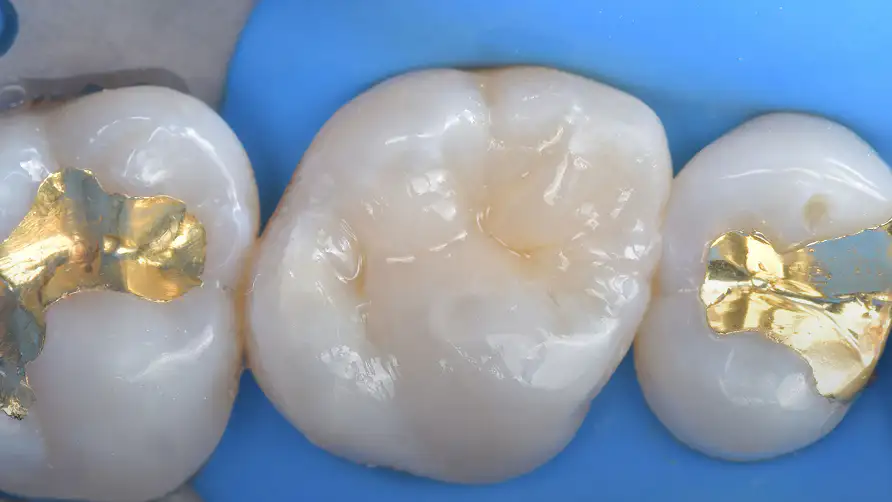

해부학적 형태의 정밀 복원

간접 수복은 구강 외에서 수작업으로 보철물을 제작합니다. 정교하게 치아의 해부학적인 형태를 복원하고, 교합 관계를 회복시킵니다.

안정적인 치료 결과를 위한 화학적인 내면 처리

보철물이 치아와 하나로 결합하기 위해서는 보이지 않는 표면의 상태가 중요합니다. 세라믹 내면의 산 부식 처리(etching)와 실란(silane)의 처리 등 과학적인 표면 처리를 통해, 탈락과 파절을 방지하는 강력한 화학적 결합을 이끌어냅니다.